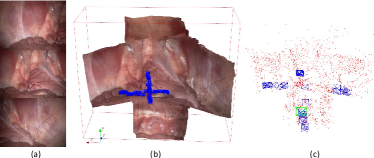

For the first set of experiments, we obtained intraoperative stereo microscope images during a neurosurgery case. The dual channel output from a Carl-Zeiss microscope was captured using an Epiphan video capture card (DVI2PCI Duo) using the 3D Slicer software [42]. Five image frames with resolution with small overlap between the frames were used to create a high-resolution mosaic of the surgical cavity. The results of the stereo reconstruction and mosaicking algorithms are shown in Fig. 10. In this experiment, we simply set the pose threshold to determine key frames to a small number hence all five images were used as key frames. Such a high-resolution mosaicking of the neurosurgery cavity could conceivably be used to register the intraoperative or diagnostic MRI to the mosaicked stereo reconstruction of the surgical cavity to identify remnant brain tumor during surgery. Due to the too small number of images, we did not run ORB-SLAM2 for this case.